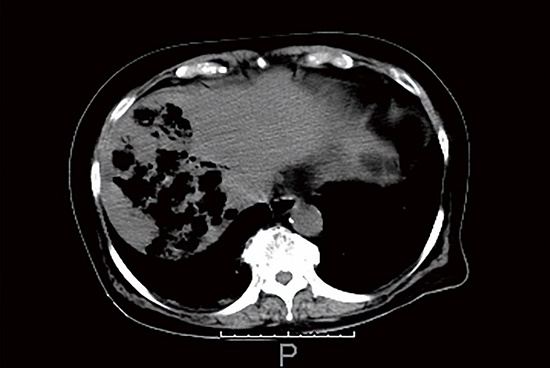

At presentation, she was lethargic, but easily arousable. Initial vital signs were: blood pressure 127/48 mmHg; pulse 109 beats per minute; respiratory rate 21 breaths per minute; axillary temperature 38.4 °C; and oxygen saturation 92% on ambient air. Physical examination revealed a well-nourished, elderly woman who presented with pallor and mild jaundice. A systolic ejection murmur (Levine grade II/VI) was audible on the heart, and the lungs were clear to auscultation. Her abdomen, which showed a midline laparotomy scar, was distended and diffusely tender, but soft with no peritoneal signs. The extremities and skin were unremarkable. The patient’s peripheral blood was hemolyzed and the serum appeared exceptionally bright red, which was consistent with marked hemoglobinemia; that is, massive intravascular hemolysis (MIH) (Figure 1). The initial laboratory data measured by automated photometric assays are shown in Table 1. Anemia with non-physiologically reduced mean cell volume (MCV) and raised mean cell hemoglobin concentration (MCHC) was identified. No urine was obtained for urinalysis because the patient was anuric. Computed tomography (CT) of the abdomen revealed multiple gas-filled necrotic cavities in the right lobe of the liver (Figure 2) as well as distention of the small intestine. The former suggested liver abscesses. Soon after undergoing CT imaging, the patient presented with hypotension and bradycardia, rapidly deteriorated with agonal respirations and required orotracheal intubation and mechanical ventilation. Under the diagnosis of liver abscess and sepsis, fluid resuscitation was performed and intravenous treatment with 0.5 g of meropenem was started after taking two sets of blood cultures. Hypotension and bradycardia persisted in spite of adequate fluid resuscitation and increasing doses of catecholamine, and she eventually collapsed. Cardiopulmonary resuscitation (CPR) was unsuccessful and she died 2.5 hours after admission. After death, the peripheral blood smear that was prepared antemortem with Giemsa staining, revealed numerous spherocytes, “dehemoglobinized” ghost cells, debris of the red cell membrane, and a few erythroblasts; intact red cells were rarely identified (Figures 3A, 3B). There was no evidence of microangiopathy or parasitic infection indicating malaria or babesiosis. Occasionally, some “boxcar-shaped” bacilli were clearly identified in the same peripheral blood smear (Figure 3B). The blood cultures grew Clostridium perfringens (C. perfringens), Escherichia coli and Enterococcal species. The autopsy was carried out 5 hours after death.